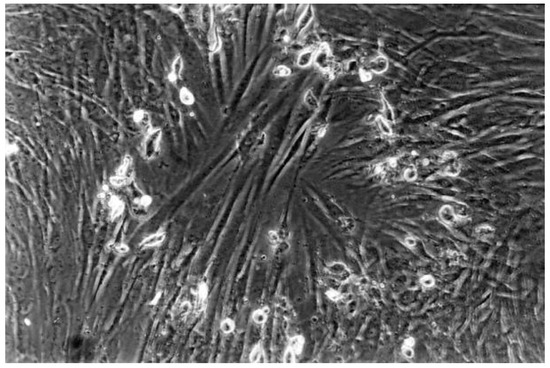

| 1 | slight | Not more than 20% of the cells are round, loosely attached and without intracytoplasmatic granules, or show changes in morphology; occasional lysedcells are present; only slight growth inhibition observable |

| 2 | mild | Not more than 50% of the cells are round, devoid of intracytoplasmatic granules, no extensive cell lysis; not more than 50% growth inhibition observable |

| 3 | moderate | Not more than 70% of the cell layers contain rounded cells or are lysed; cell layers not completely destroyed, but more than 50% growth inhibition observable |

| 4 | severe | Nearly complete or complete destruction of the cell layers |